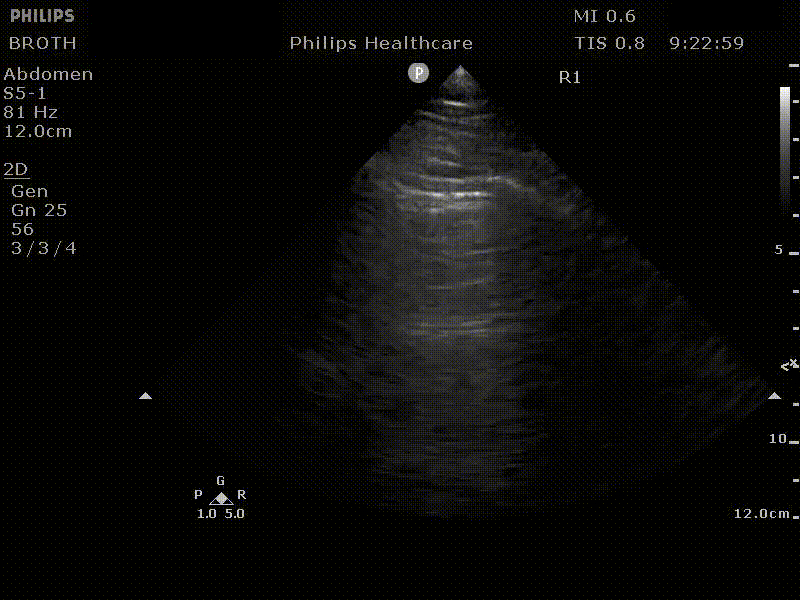

Mirror artefact and the diaphragm: Look at the image below on the left, is there a pleural effusion above the liver? No! Then what is that dark grey above the diaphragm? What we are seeing is a mirror artefact. The ultrasound beam reflects off of the diaphragm strikes the liver parenchyma then returns to the transducer. Due to the increased time the echo took to return the computer interprets this and renders an image showing liver parenchyma below the diaphragm; its an error but can look like an effusion. To distinguish between mirror-artefact and effusion look for the spine! An effusion creates a window to the spine that would ordinarily be sacred by lung tissue. If you see anechoic material and spine below you have an effusion. If you don’t see the spine you cannot rule in an effusion.